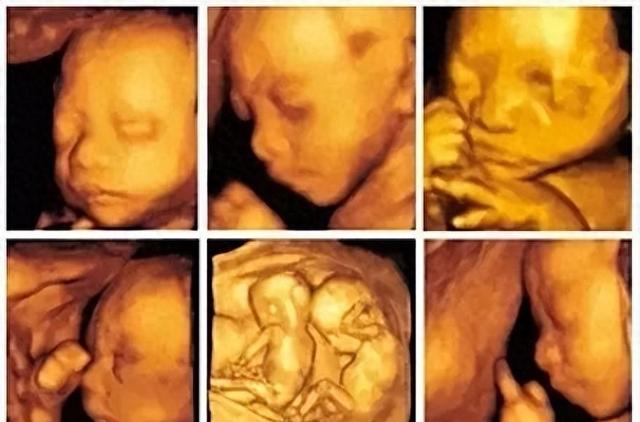

每位准妈妈怀孕的时候都有个大排畸检查,这可重要了,好多人听过这检查,可到底查什么、什么时候查、查出来有问题咋办,都不太明白,实际上大排畸就是给胎儿做超声检查,看看宝宝身体结构发育正不正常,能不能发现先天性畸形。 不管...